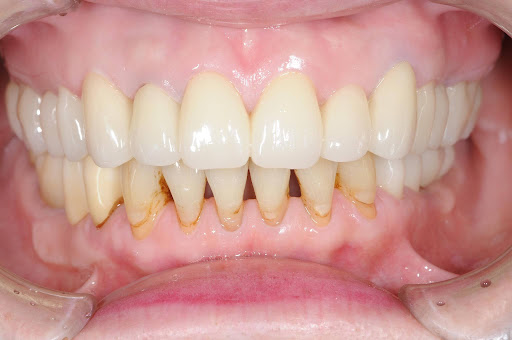

| 主訴 | 全顎治療希望、全顎的に歯が動く、奥の歯がなくて噛めない。できるだけ綺麗で噛めるようになりたい。 |

| 治療内容 | 全顎的に歯周病、前歯部の被蓋が深く、重度歯列不正が認められるため、 歯周外科を含む歯周治療、矯正治療、インプラント治療、セラミックによる補綴治療後メインテナンスに移行しました。 |

| 治療費 | 5,060,000円(税込)(インプラントすべて含む) |

| 治療期間 | 2年4ヶ月 |

| 治療回数 | 90回 |

| 想定されたリスク | 矯正治療の後戻り、歯周病の再発、食いしばり(パラファンクション)によるセラミックの破折、歯の破折のリスクがありました。 |